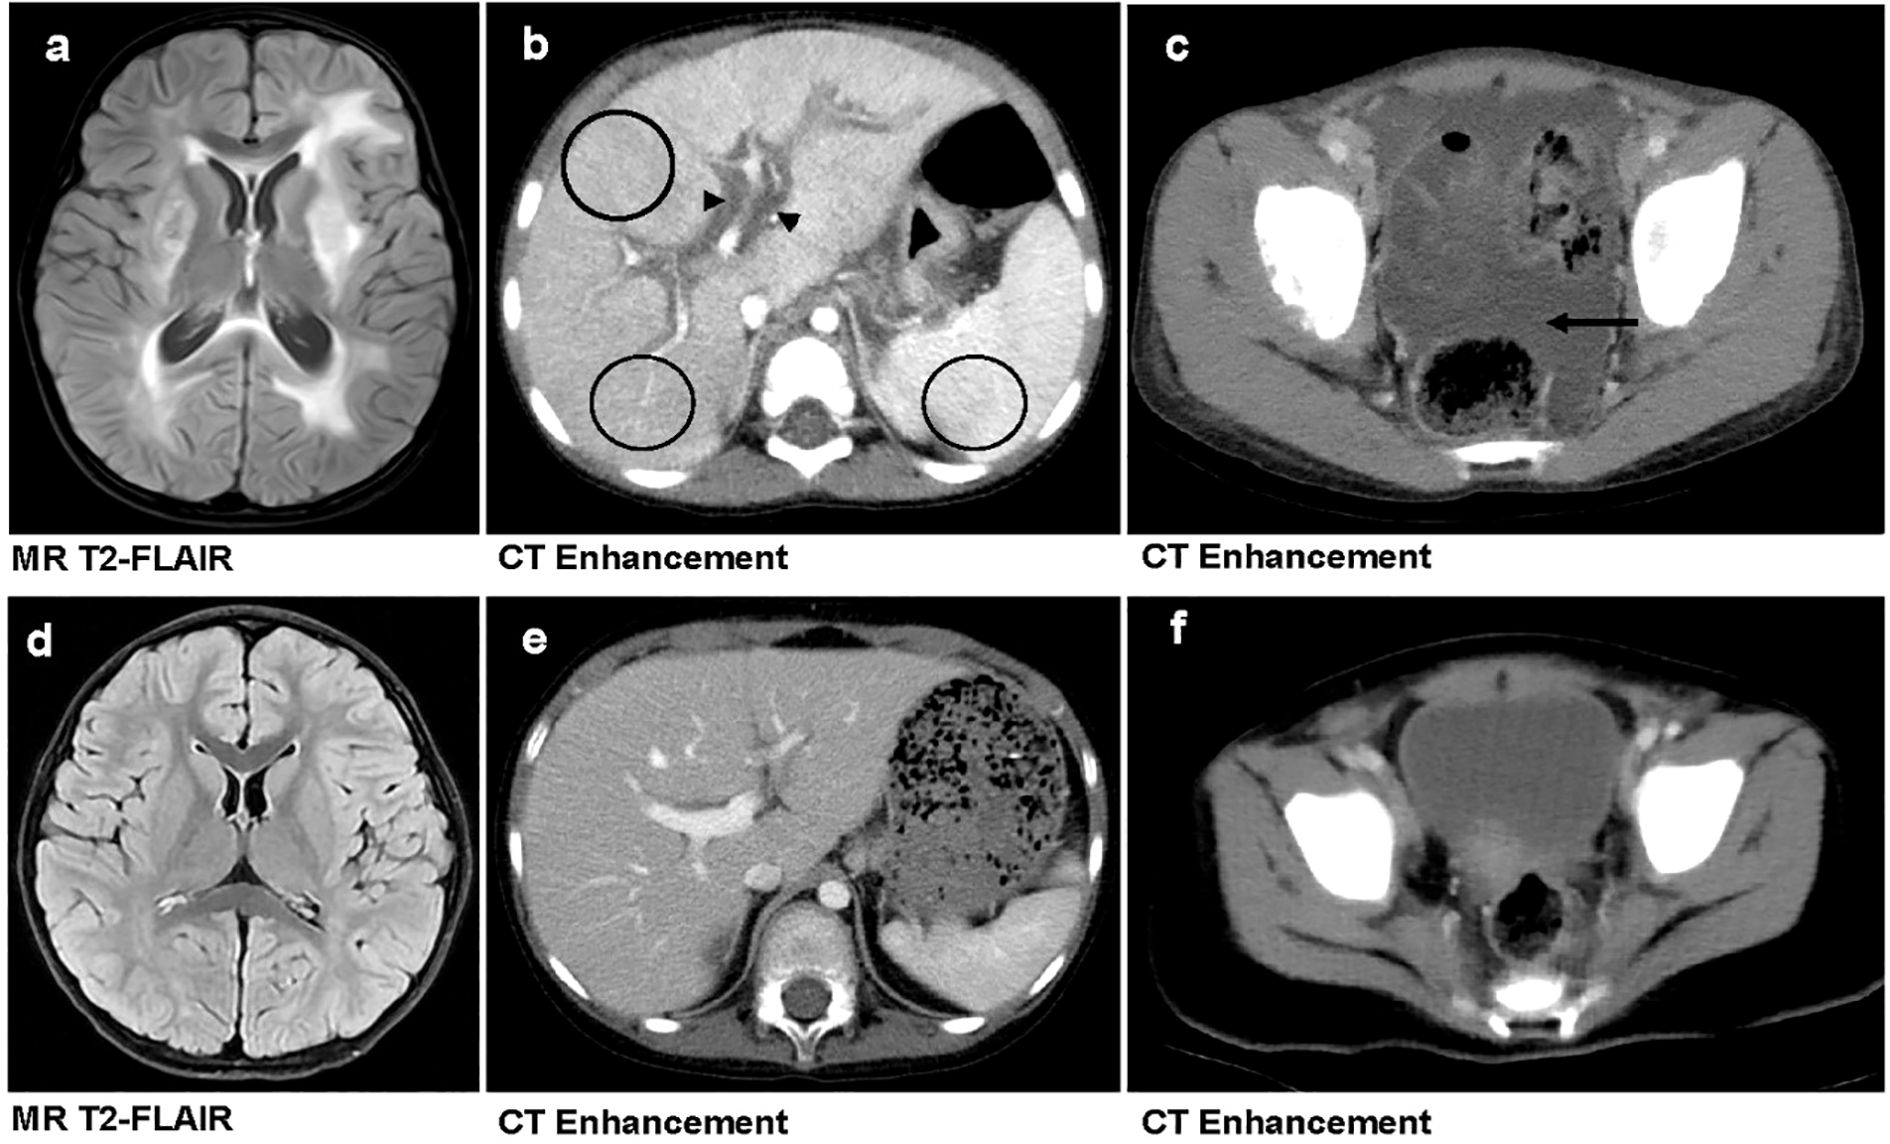

Univariate Cox regression analysis of five laboratory variables and nine imaging variables indicated that severe anemia (Hb<30 g/L), severe thrombocytopenia (PLT<50×109/L), severe CNS involvement, hepatic interstitial edema, heterogeneous liver/spleen enhancement, and massive ascites were significantly associated with poor outcomes in children with HLH (Table 3). Multivariate analysis further confirmed that severe thrombocytopenia (HR = 2.93, 95%CI:1.62-5.30, p < 0.01), severe CNS involvement (HR = 1.80, 95%CI:1.14-2.84, p = 0.01), heterogeneous liver/spleen enhancement (HR = 2.78, 95%CI:1.85-4.18, p < 0.01), and hepatic interstitial edema (HR = 1.75, 95%CI:1.22-2.51, p < 0.01) as independent risk factors for HLH-related mortality (Table 3). Figure 3 illustrates the distinct imaging manifestations of these risk factors in two HLH pediatric cases with differing clinical outcomes.

Figure 3

Comparison of imaging findings between primary and secondary HLH in pediatric patients. (a–c) A 3-year-old girl with primary HLH (genetic defect: UNC13D, familial HLH type 3 [FHL3]) who succumbed to the disease. Brain MRI reveals widespread bilateral T2-FLAIR hyperintensities, indicative of parenchymal involvement (a). Contrast-enhanced abdominal CT demonstrates hepatic interstitial edema (marked by black triangles) and heterogeneous hepatosplenic enhancement (highlighted by black circles) (b). Contrast-enhanced pelvic CT shows massive ascites (indicated by black arrow) (c). (d–f) A 3-year-old boy with secondary HLH who survived. Brain MRI (d), contrast-enhanced abdominal CT (e), and Contrast-enhanced pelvic CT (f)—all show no significant abnormalities.